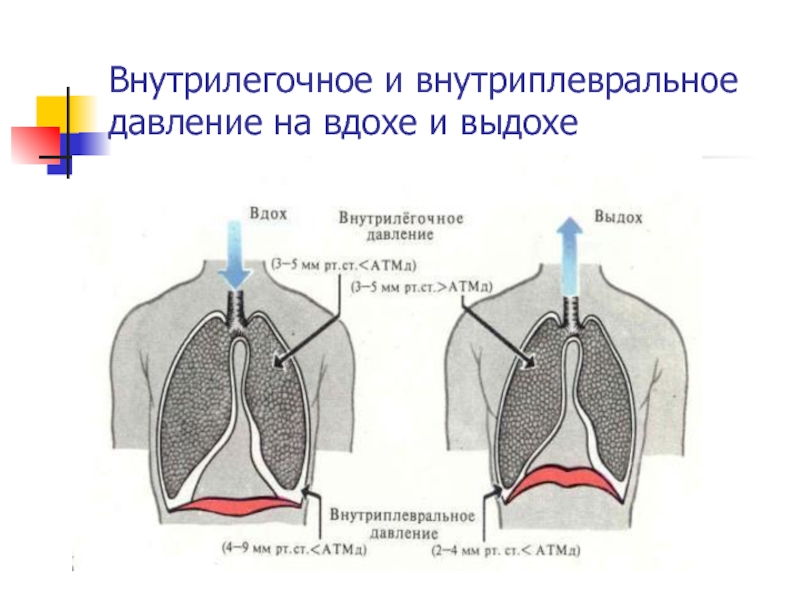

Схемы дыхания: Пневмоторакс на изображениях